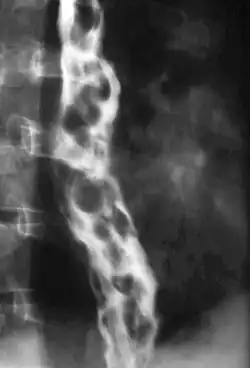

Esophageal varices are extremely dilated sub-mucosal veins in the lower third of the esophagus.[1] They are most often a consequence of portal hypertension,[2] commonly due to cirrhosis.[3] People with esophageal varices have a strong tendency to develop severe bleeding which left untreated can be fatal. Esophageal varices are typically diagnosed through an esophagogastroduodenoscopy.[4]

The upper two thirds of the esophagus are drained via the esophageal veins, which carry deoxygenated blood from the esophagus to the azygos vein, which in turn drains directly into the superior vena cava. These veins have no part in the development of esophageal varices. The lower one third of the esophagus is drained into the superficial veins lining the esophageal mucosa, which drain into the left gastric vein, which in turn drains directly into the portal vein. These superficial veins (normally only approximately 1 mm in diameter) become distended up to 1–2 cm in diameter in association with portal hypertension.

Normal portal pressure is approximately 9 mmHg compared to an inferior vena cava pressure of 2–6 mmHg. This creates a normal pressure gradient of 3–7 mmHg. If the portal pressure rises above 12 mmHg, this gradient rises to 7–10 mmHg.[5] A gradient greater than 5 mmHg is considered portal hypertension. At gradients greater than 10 mmHg, blood flowing through the hepatic portal system is redirected from the liver into areas with lower venous pressures. This means that collateral circulation develops in the lower esophagus, abdominal wall, stomach, and rectum. The small blood vessels in these areas become distended, becoming more thin-walled, and appear as varicosities.

Dilated submucosal veins are the most prominent histologic feature of esophageal varices. The expansion of the submucosa leads to elevation of the mucosa above the surrounding tissue, which is apparent during endoscopy and is a key diagnostic feature. Evidence of recent variceal hemorrhage includes necrosis and ulceration of the mucosa. Evidence of past variceal hemorrhage includes inflammation and venous thrombosis.